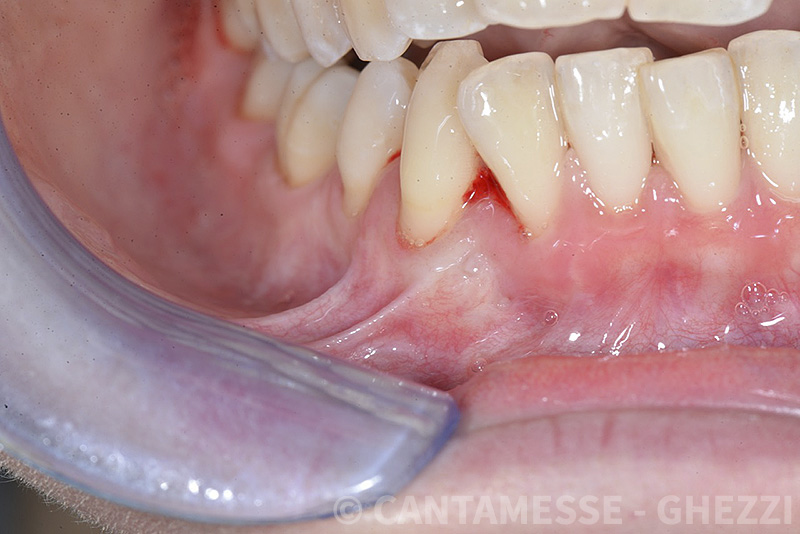

PREMESSA: in seguito all’estrazione dell’incisivo laterale superiore di destra, resasi necessaria per cause batteriche, si decide di affrontare il caso con il posizionamento di un impianto in sostituzione dell’elemento mancante dopo guarigione del sito infetto. Con tecniche rigenerative sia dei tessuti ossei mancanti a causa dell’infezione pregressa, sia dei tessuti gengivali che appaiono inizialmente troppo spostati in alto, si ripristina una corretta morfologia delle parabole (contorni) gengivali e delle papille interdentali (triangoli di gengiva tra due denti vicini).